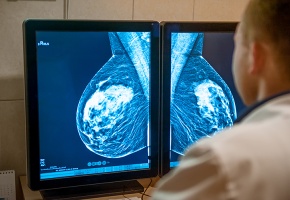

Dépistage du cancer du sein : la mammographie par tomosynthèse est-elle sure ?

La tomographie est une technique d’imagerie qui peut être associée à la mammographie ; elle permet alors de reconstituer un cliché en trois dimensions à partir d’images du sein obtenues sous différentes coupes (ou projections). Elle est donc parfois présentée sous le nom de « mammographie 3D ». « Mais en réalité l’appareil ne tourne que de façon limitée autour du sein et l’image totale de celui-ci est reconstruite grâce à un algorithme mathématique à partir des projections obtenues » précise la HAS. Ces dernières années, les cabinets de radiologies se sont équipés de mammographie par tomosynthèse, « sans que la pertinence d’intégrer cette technologie dans le cadre du dépistage organisé n’ait été évaluée » note l’autorité de santé. Il est donc apparu nécessaire d’en évaluer l’intérêt et les risques potentiels dans le cadre de ce dépistage. Dans ce cadre, la HAS a publié le 27 novembre un premier travail (volet 1) qui fait le point sur la performance de la mammographie par tomosynthèse à partir d’une revue de la littérature internationale. Il en ressort que cette technique améliore le taux de détection des cancers (in situ et invasifs). Pour la HAS, plusieurs questions restent cependant sans réponse pour le moment. Cela concerne notamment le bénéfice à introduire la mammographie par tomosynthèse dans le dépistage organisé ; la sécurité liée à la dose d’exposition aux rayons X ; l’homogénéité de performance d’une machine à une autre ; et les conditions de mise en œuvre de la double lecture. Ces questions sont examinées dans le volet 2 de l’évaluation de la HAS en vue de se prononcer sur l’intérêt d’intégrer la mammographie par tomosynthèse dans le dépistage organisé. Cette deuxième partie de l’évaluation devrait être publiée en fin d’année 2020.